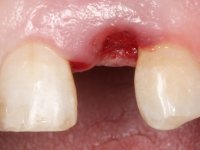

One year after the last intervention, a third reason appeared for the third phase of treatment: a fracture on the feldspathic veneer placed on tooth 2.1.

• Confection and bonding of a new feldspathic veneer to replace the fractured one. The new veneer should include a greater distal inter-proximal dental area from tooth 2.1.

The axis of insertion of the veneer in relation to the abutment was very carefully evaluated. The feldspathic veneers were prepared in the laboratory and then bonded to the mouth after placing absolute insulation. One year later, we began our third phase of treatment, after the veneer in tooth 2.1 fractured. A dental preparation was done on the bonded veneer, seeking to extend the distal inter-proximal interface more to the palate. The objective would be to move the veneer to a more palatine contact point. Preparation of tooth 1.2 was limited to creating an insertion axis. After preparation, the total crown and laboratory veneer were bonded to the mouth. First, the crown was bonded using a relative insulation with Teflon, later the veneer was bonded after the absolute insulation placement. In the crown, I used this type of insulation to avoid the use of staples. It would be difficult to apply due to the shape and size of the tooth, and would also be aggressive to the soft tissues. After bonding procedures, the occlusal integration of the work was evaluated.